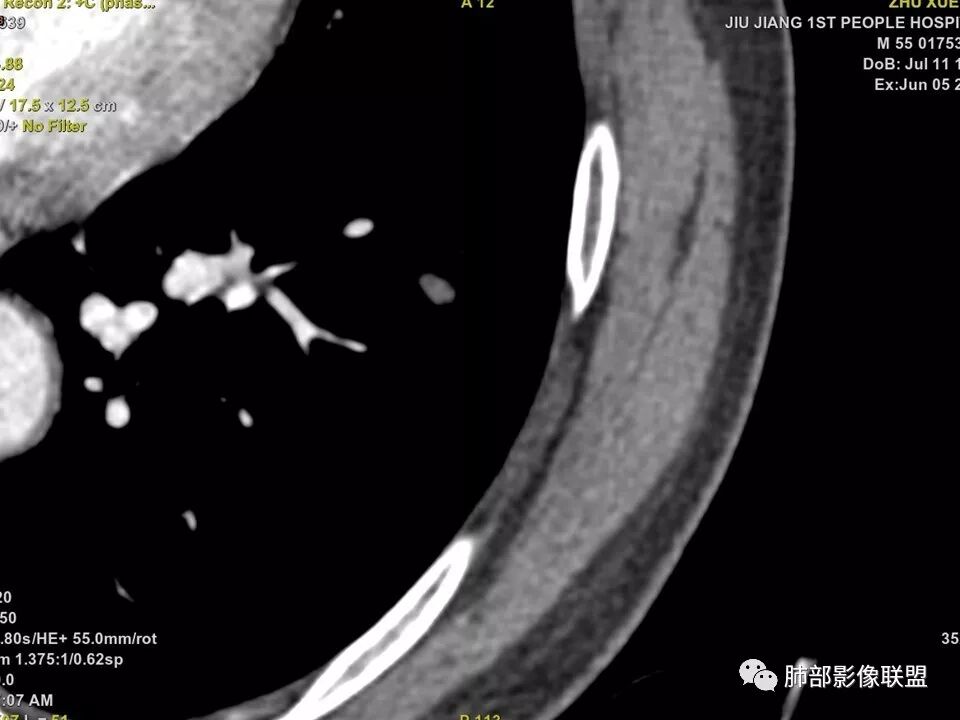

边缘有光滑,有圈黑晕,强化弱,似乎有脂肪密度,支气管截断的部位很自然,没有鼠尾状狭窄,考虑软骨型错构瘤?

这个支气管开口位置,如果是肿瘤应该有管壁浸润,也应该有膨胀感,这个没有,不像恶性肿瘤的支气管截断

不是假象,是真的堵了,我工作站薄层做了气管曲面重建,仿真内窥镜也显示堵了

也咨询了病理科老师,肺软骨瘤来源于支气管透明软骨,理论上可以从黏膜下,突向支气管腔内生长,对支气管造成压迫性的阻塞。影像上和软骨瘤样错构瘤没法区分

肺软骨瘤好发年龄40~50 岁,男女发病无明显差异。多位于两肺外带,右肺多见。无明显临床症状,常在体检时偶然发现。若病灶发生于大支气管壁或病灶较大压迫支气管时(少见)可引起刺激性咳嗽、咳痰等症状。

典型CT特征包括:(1)圆形或椭圆形边界清楚的病灶。(2)大小1~4cm,有轻微分叶改变。(3)较均匀的软组织影,多伴有钙化。(4)无毛刺,卫星灶及肺门或纵隔淋巴结肿大。(5)CT增强扫描无强化或轻度强化,其强化可能与软骨瘤间质中的薄壁血管或周围慢性炎症反应有关。